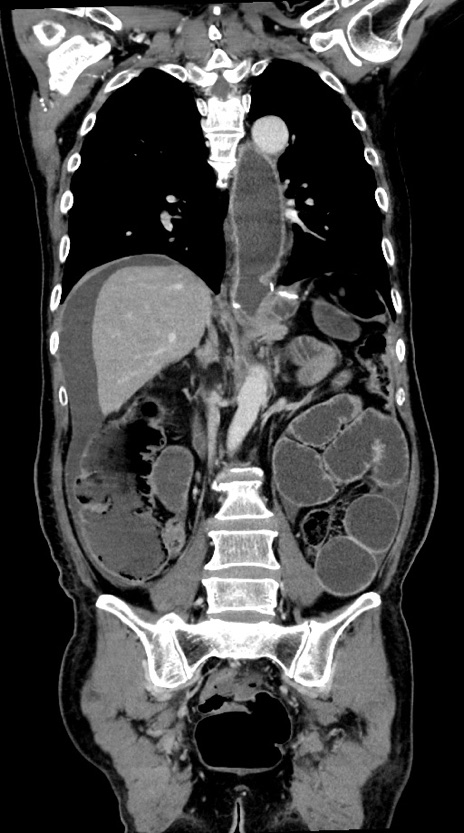

症例28(冠状断像)

【症例】60歳代男性

【主訴】嘔吐

【現病歴】胃癌にて胃全摘後。食思不振が悪化し、夜中に嘔吐することがある。

【既往歴】胃癌、胃全摘、脾摘、胆摘後

【データ】WBC 5900、CRP 10.56